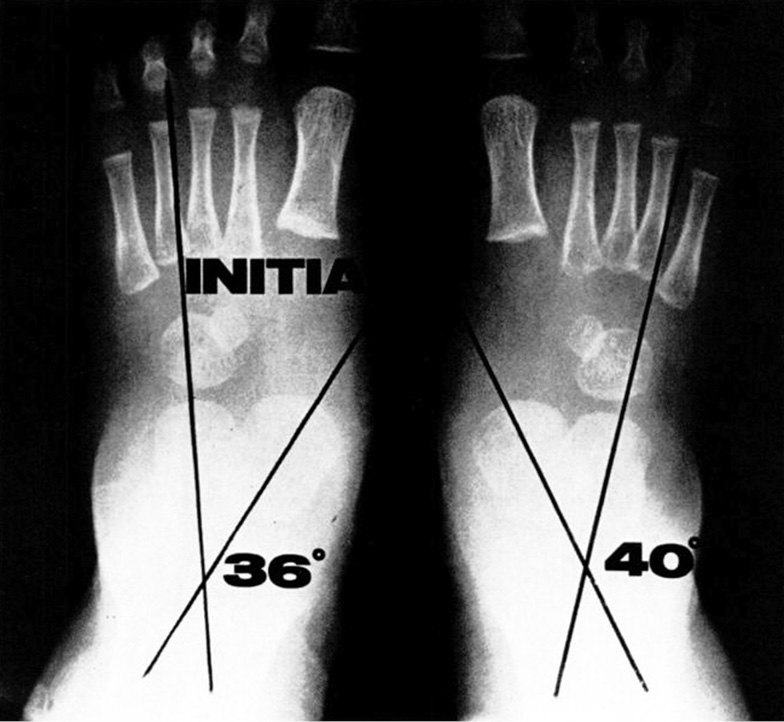

Рис. 3-B. Типичный пациент. Исходная рентгенография стоп в положении «стоя», переднезадняя проекция: таранно-пяточный угол — справа 40°, слева 36°

Традиционно измеряемый таранно-пяточный угол (рис. 3-B) также оценивали в начале исследования, но его не использовали в качестве критерия промежуточной оценки по причине сложности интерпретации по переднезадним рентгенограммам, которые выполняли в коррекционной обуви со стальным геленком.